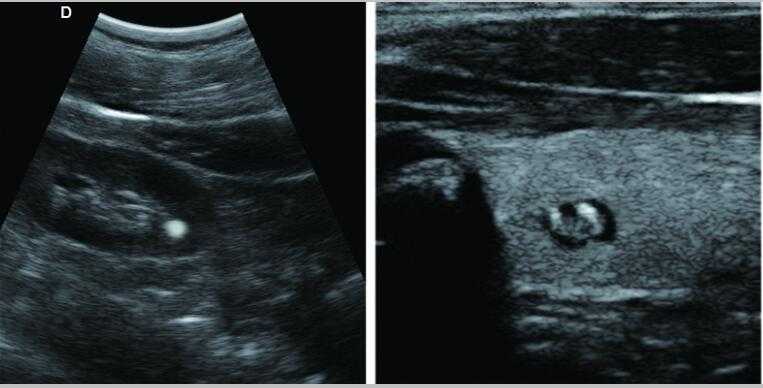

L3-VET筆記本式獸用B超機

L3-VET便攜筆記本式獸用B超機適用探頭